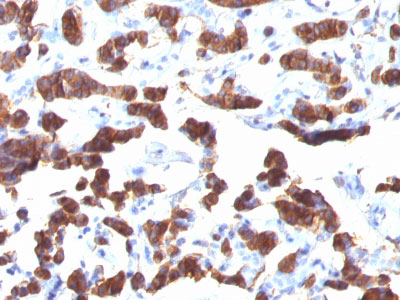

Formalin-fixed, paraffin-embedded human Thyroid Carcinoma stained with Thyroglobulin Monoclonal Antibody (TGB24). |